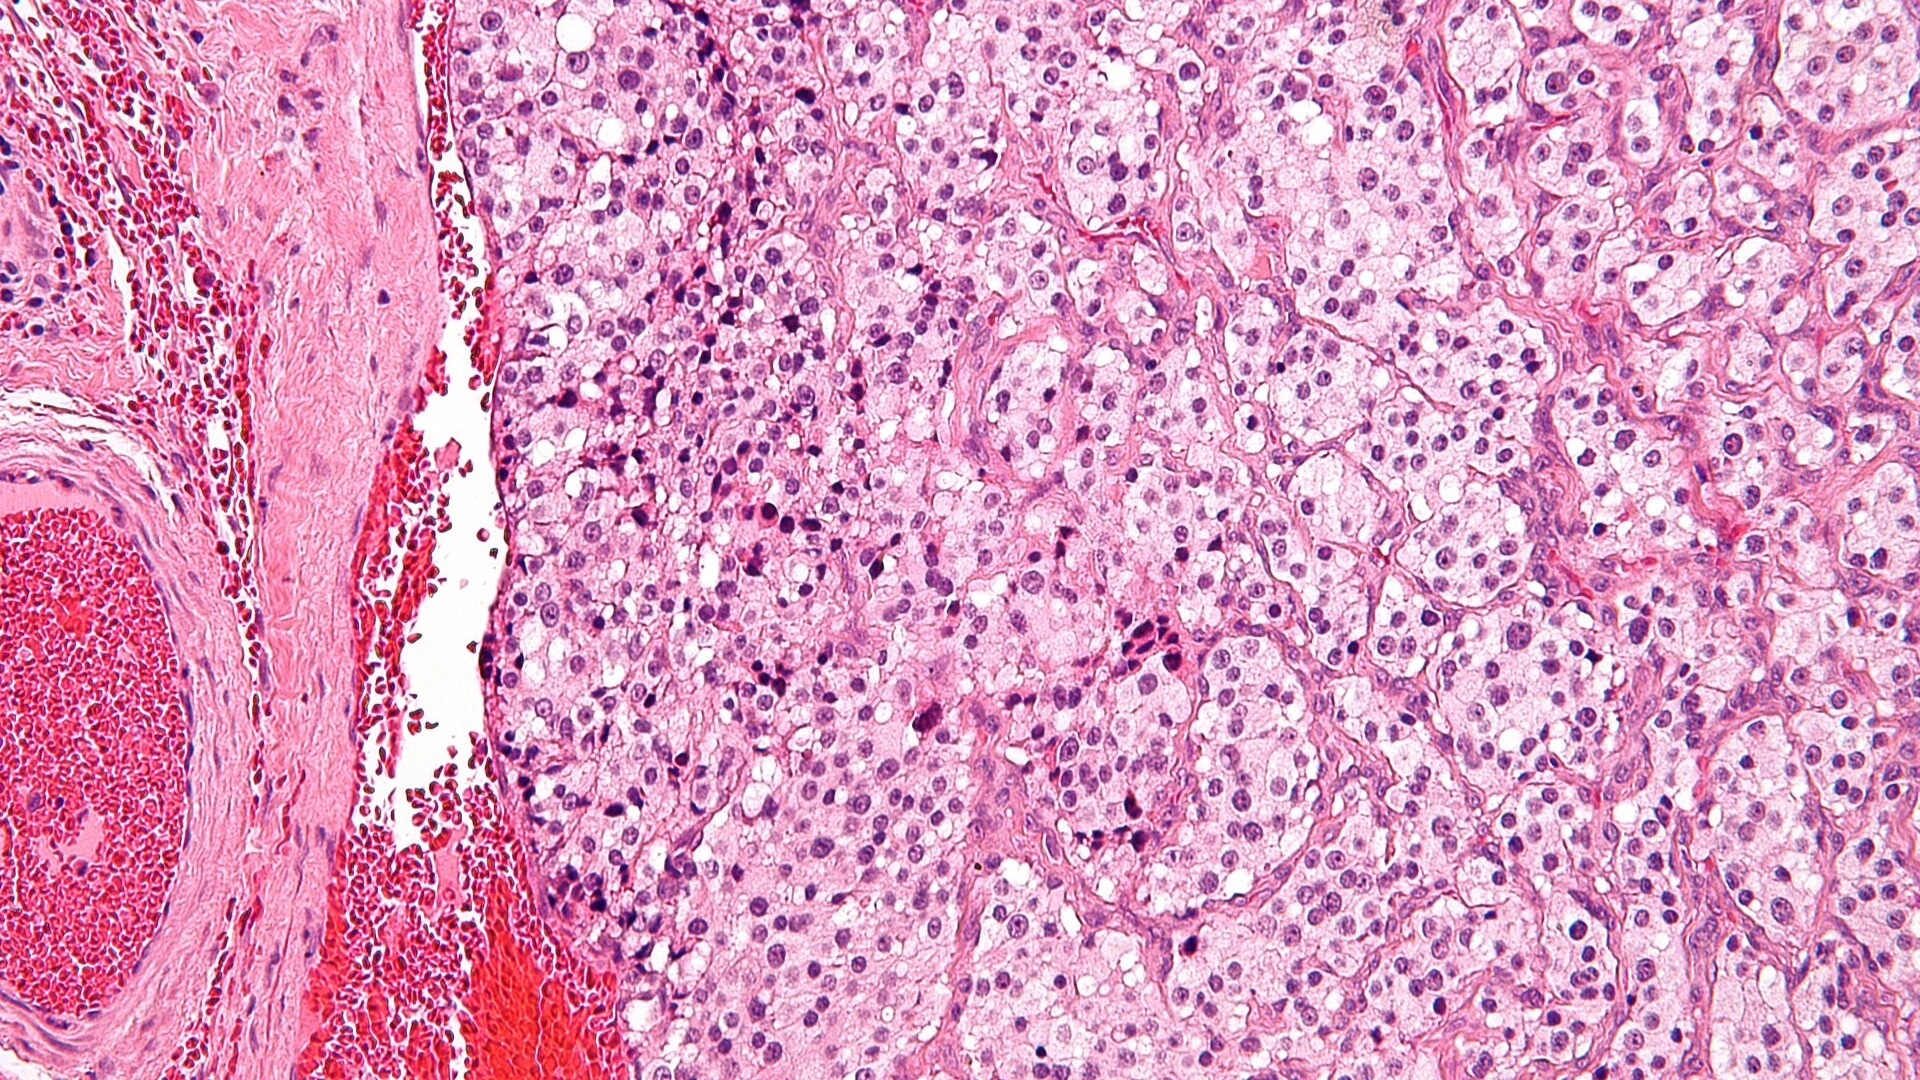

Paraganglioma is an uncommon neuroendocrine tumor arising from chromaffin cells within paraganglia. These specialized cells often regulate essential body functions, such as blood pressure, heart rate, and stress responses, by secreting catecholamines like adrenaline and noradrenaline.

One defining biological characteristic observed in Paragangliomas is their reliance on altered glucose metabolism. Utilizing glycolysis in hypoxic or non-hypoxic environments gives cancer cells a significant growth advantage, evident in substantial glucose uptake visible during diagnostic PET scans (18F-FDG imaging). Targeted therapies exploiting cancer cells’ glucose dependency, known as metabolic oncology, are instrumental for treatment innovation, supported by Nobel-winning research (Allison, Semenza).